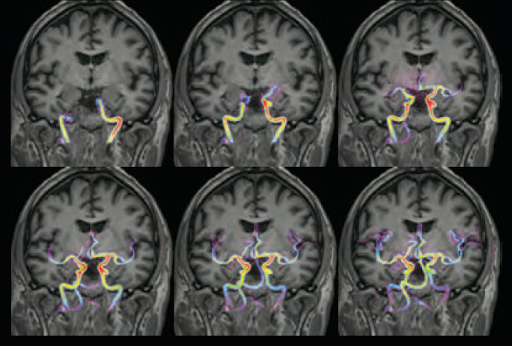

Оценка гемодинамики с помощью MUTE 4D MRA

Технология UTE от Vantage Galan 3T обеспечивает меньшую дефазировку и позволяет получить более однородные сигналы от сосудов. Система позволяет визуализировать кровоток без необходимости использования контрастных веществ.

МРТ без контрастирования

В последнее время все больше внимания уделяется изучению потенциальных рисков, связанных с контрастными веществами на основе гадолиния. Технологии, позволяющие проводить полноценное МРТ-исследования без контраста, сводят к минимуму риск для пациентов с чувствительностью к веществам для контрастирования, при этом не снижая качество диагностики.